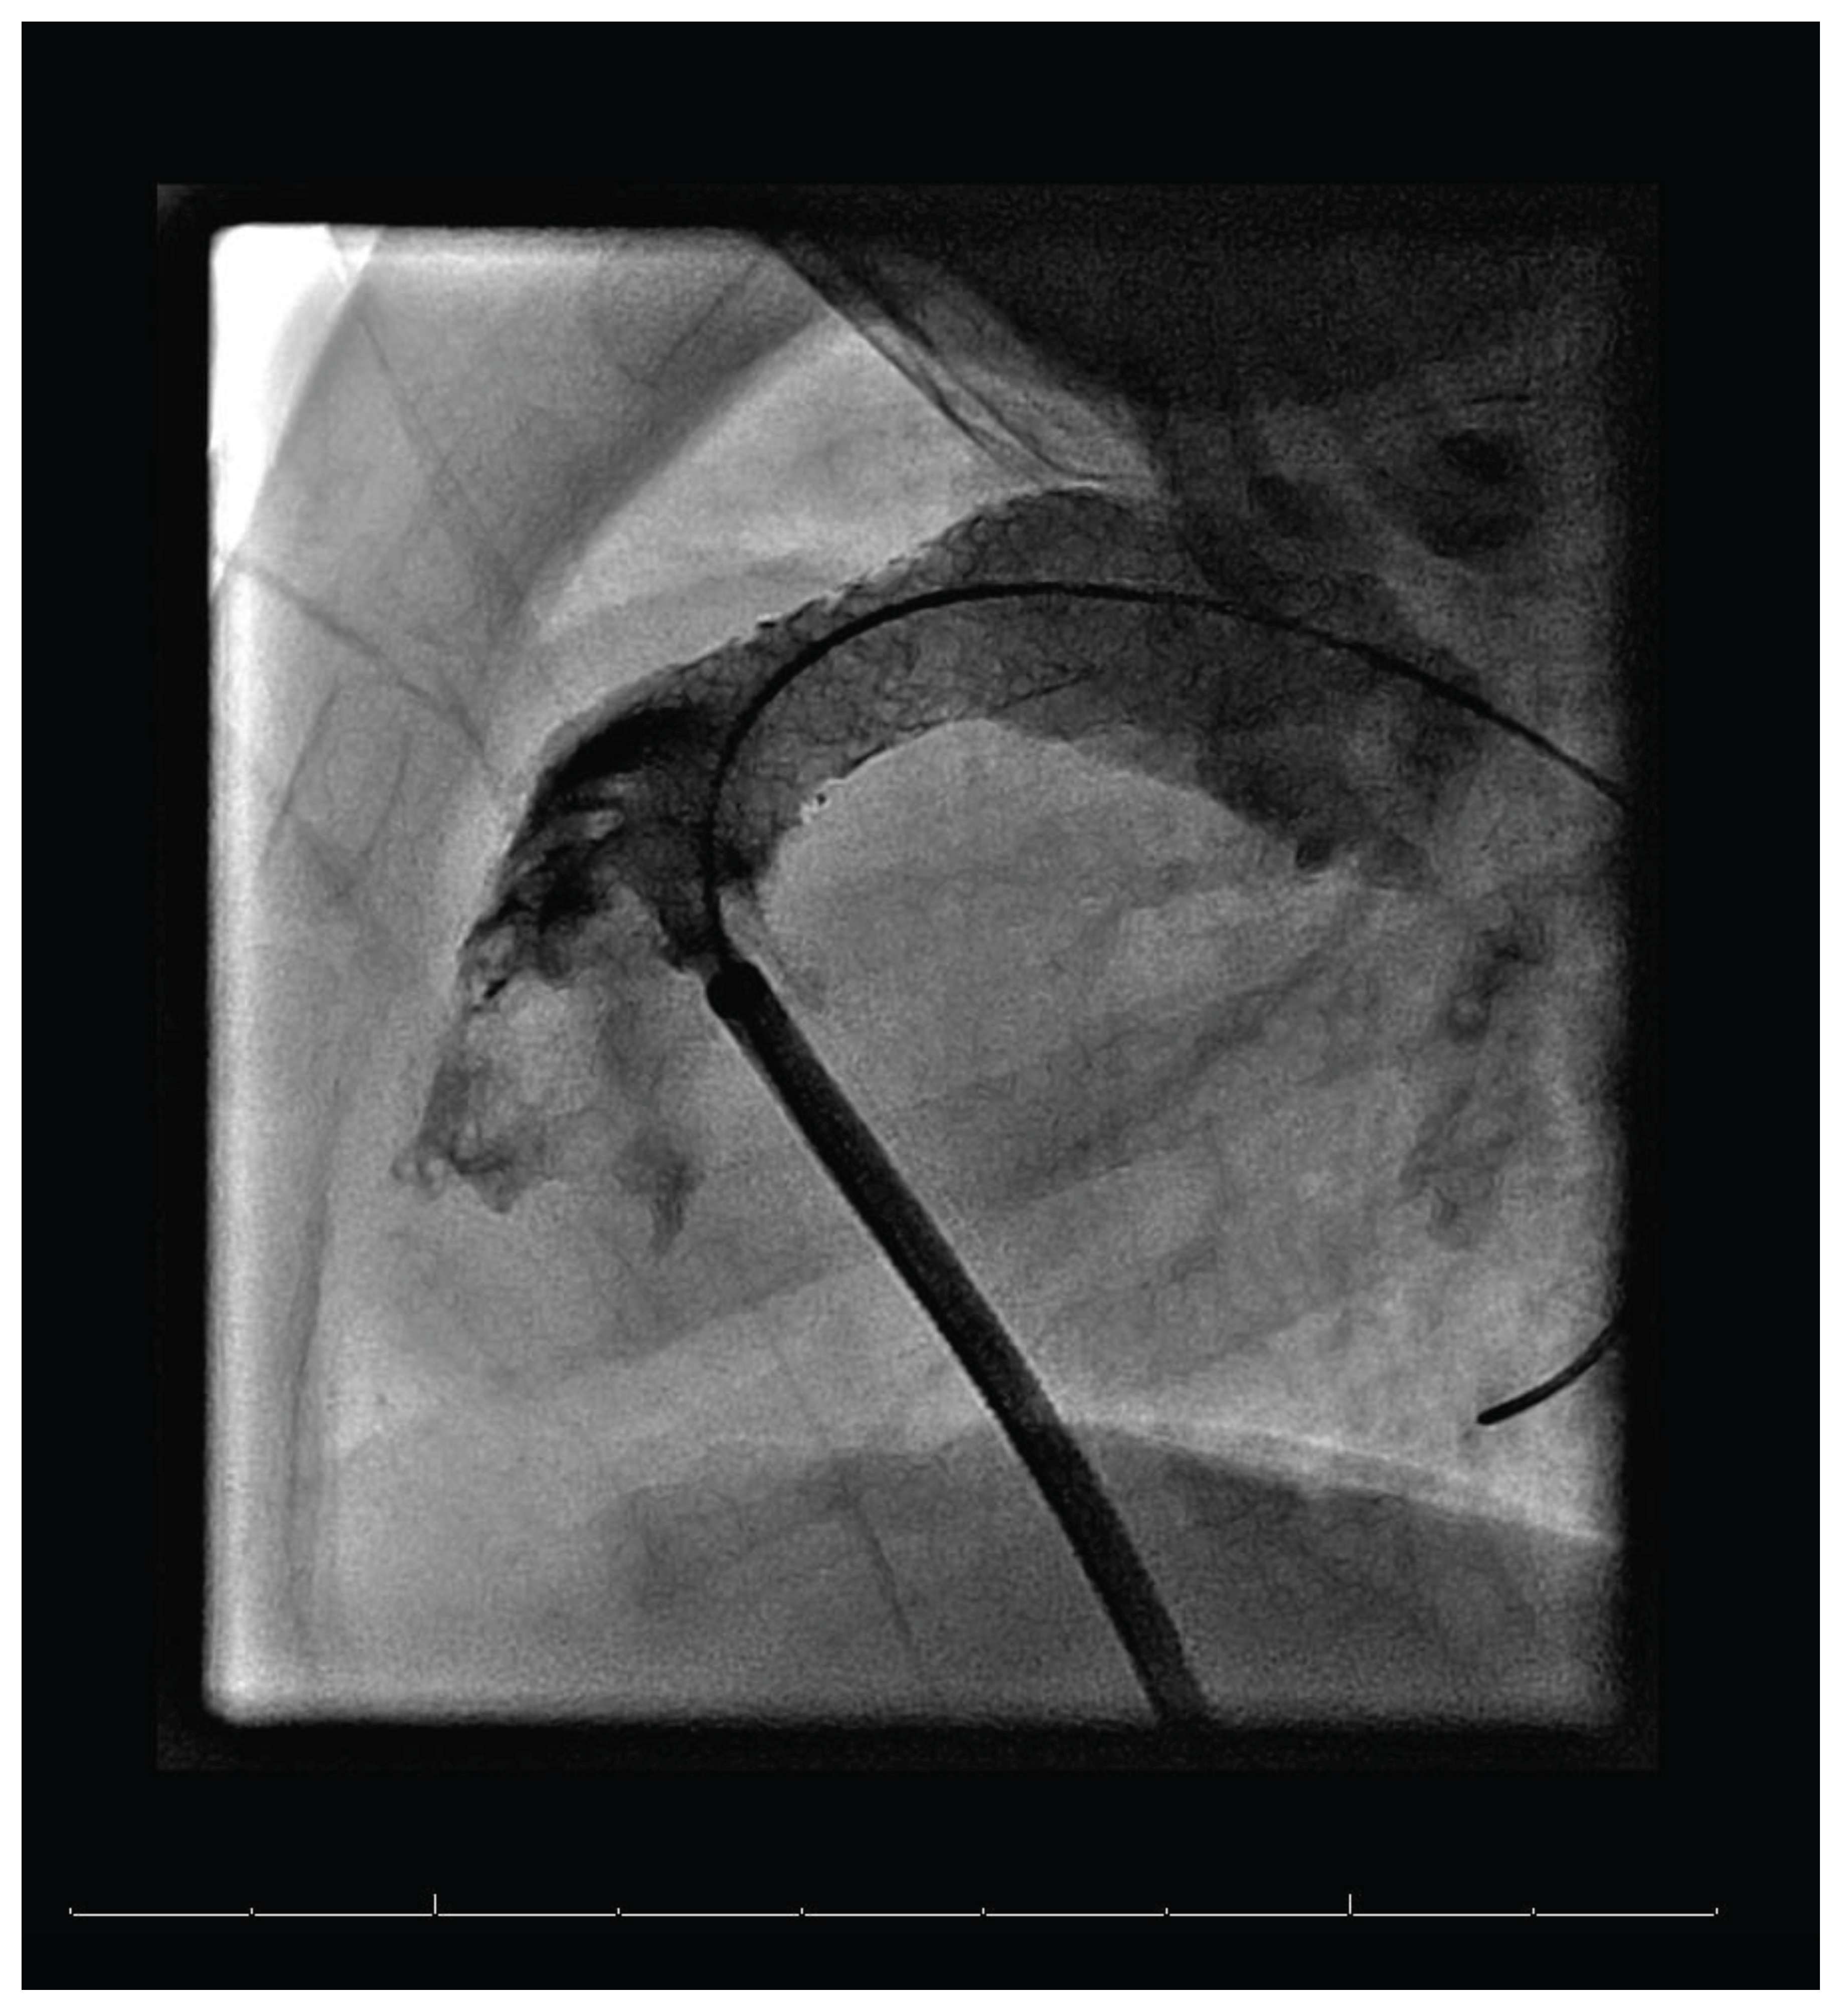

Figure 3. Lateral imaging of RVOTO after stent implementation, taken from 3D angiography.